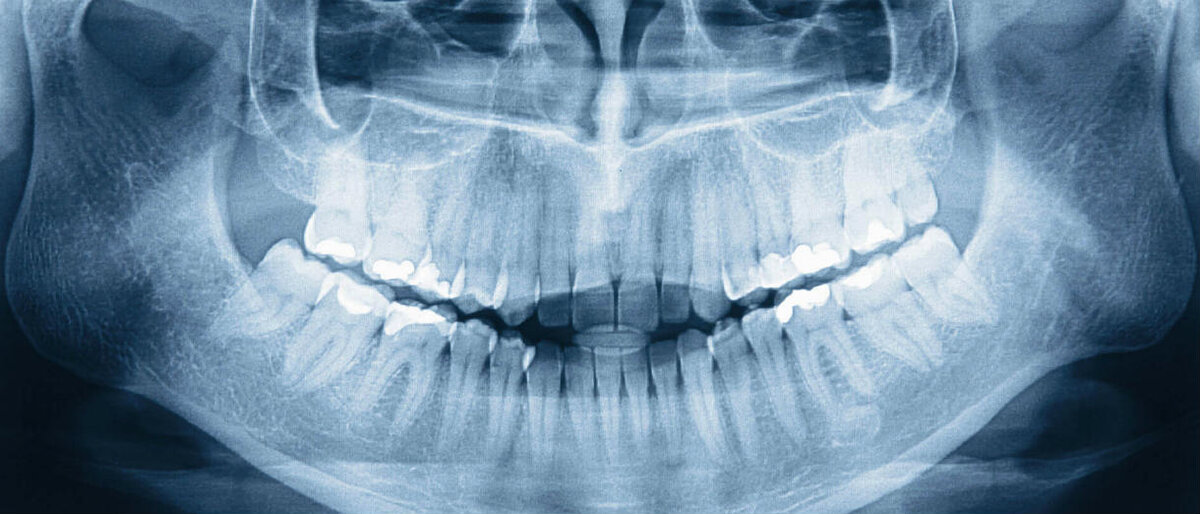

Благодаря развитию технологий, в стоматологии появились новые методы исследования зубного ряда и диагностирования заболеваний. Наиболее современным на сегодняшний момент является ортопантомограмма (ОПТГ) или, по-другому, панорамный рентгеновский снимок зубов. На полученном изображении отчетливо видны два ряда зубов, челюстное строение, верхнечелюстной сустав и носовые пазухи. Благодаря снимку, врач сможет диагностировать дефекты прикуса и верхнечелюстного сустава, состояние костной ткани и общую картину строения челюсти в целом. Показания к проведению ортопантомограммы зубов Пациента направляют на процедуру для диагностики: Существует два типа аппаратов ОПТГ — пленочный и цифровой. Пленочный метод получения фото зубов устарел и сейчас редко используется, его главный минус в длительности процедуры и, как следствие, сильном облучении пациента. Цифровая ортопантомограмма более распространена в современных клиниках — процесс занимает минимум времени, а полученный результат записывается н

Благодаря развитию технологий, в стоматологии появились новые методы исследования зубного ряда и диагностирования заболеваний. Наиболее современным на сегодняшний момент является ортопантомограмма (ОПТГ) или, по-другому, панорамный рентгеновский снимок зубов. На полученном изображении отчетливо видны два ряда зубов, челюстное строение, верхнечелюстной сустав и носовые пазухи. Благодаря снимку, врач сможет диагностировать дефекты прикуса и верхнечелюстного сустава, состояние костной ткани и общую картину строения челюсти в целом.